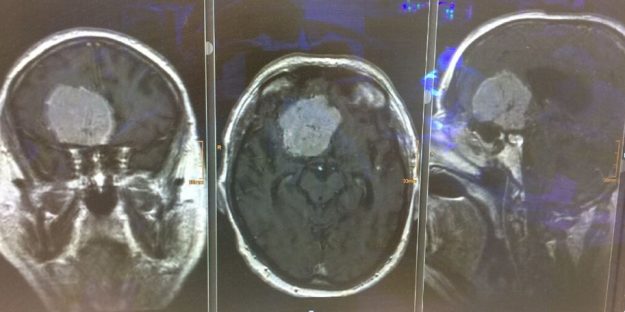

Αραχνοειδής Κύστη Εγκεφάλου

Ασθενής γυναίκα 58 ετών με πονοκεφάλους και διαταραχές όρασης. Ο οφθαλμολογικός έλεγχος έδειξε οίδημα οπτικών θηλών άμφω και σημαντικό περιορισμό των οπτικών πεδίων. Τα συμπτώματα της ασθενούς ήταν προοδευτικά επιδεινούμενα, το ίδιο και οι εξετάσεις της. Η μαγνητική εγκεφάλου ανέδειξε ευμεγέθη αραχνοειδή κύστη δεξιά κροταφικά με σημαντική πίεση επί του υγιούς εγκεφάλου και παρεκτόπιση των…